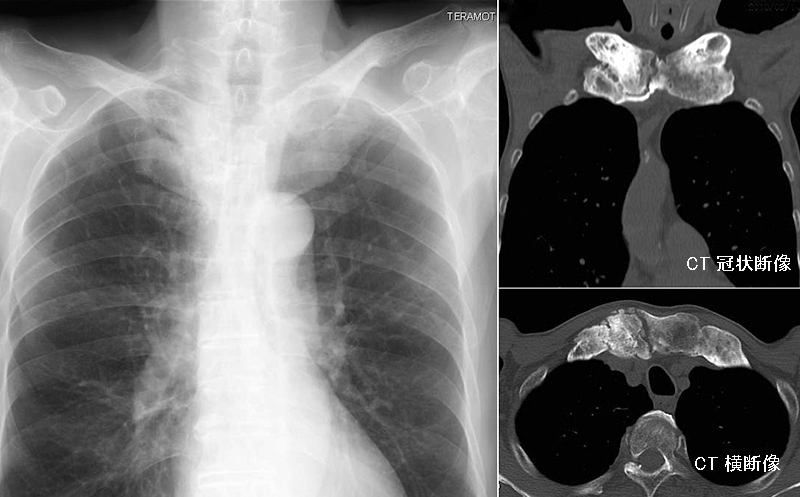

骨・関節の画像診断に特化した専門書。書き込み、マーカー等ありません。中古品になりますので、ご理解のほどよろしくお願いいたします。カイロプラクティック オステオパシー 手技理学療法 運動療法 解剖学 レントゲン